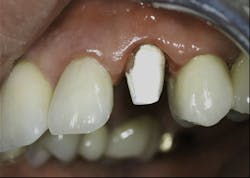

3. All supragingival coronal tooth structure gone. Endodontic treatment usually necessary. Post and core placed. Enough remaining tooth structure to allow at least 2 mm of ferrule around the margin portion of the tooth preparation, or bony crown lengthening accomplished allowing the ferrule. Nonabusive occlusion (Figures 1 and 2)-This clinical situation requires in-depth informed consent from the patient, since saving the tooth is expensive and the long-term success of the clinical result is questionable. If the treatment fails, an extraction, along with an implant and crown or a fixed prosthesis, will be required, further adding to the patient cost. The potential for success is markedly reduced in this situation. However, proper placement of a post and core and crown allows clinical success in a significant percentage of cases. If the patient feels more comfortable with an implant after proper informed consent, that treatment should be strongly considered. However, in my experience, many patients prefer to retain the affected tooth, in spite of the reduced potential for long-term service. That is also my personal preference.